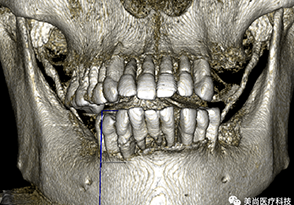

粘膜支持式的种植导板设计生产流程

• CBCT第一次扫描(病人戴着放射导板)

• CBCT第二次扫描(单独扫描的放射导板影像)

第一次CBCT数据要求 :

• 患者戴着放射义齿拍摄,放射导板在口内与黏膜完全贴合密闭

• 除放射标记点外不得有任何金属物或阻射物

• 使用非阻射材料取咬合记录

• 保证咬合完全正确且稳定,无撬动及支点